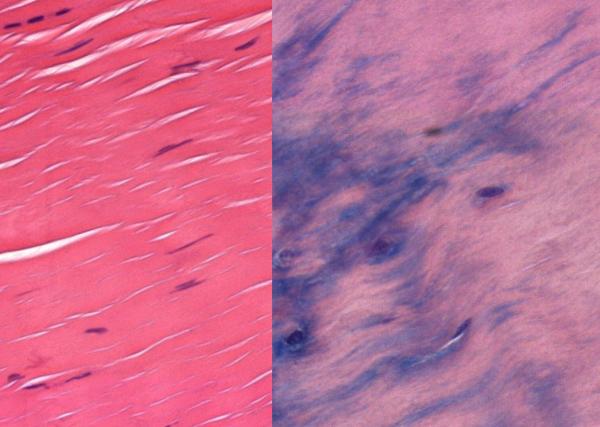

Dr. McBeath and colleagues examined tendon samples from patients who were undergoing surgery for tendinosis and compared tendons from elderly versus young patients. Under normal oxygen levels, the tendon cells retained a normal shape and flexibility. But when those cells were grown in low-oxygen levels, mimicking the low-oxygen environment common in older people, the tendon cells changed shape, and became round and more similar to tough cartilage-like cells, called fibrocartilage.